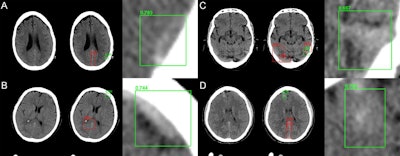

Since February 2018, the software tool has been used clinically for real-time interpretation of all head CT exams performed in the emergency room. Prospective data from one month of use showed that the algorithm identified 77 (95.1%) of 81 total cases of hemorrhage and yielded similar results to those achieved with the testing dataset.

Clinical performance of algorithm for brain hemorrhage detection | |

Accuracy | 97.2% |

Area under the curve (AUC) | 0.989 |

Sensitivity | 95.1% |

Specificity | 97.3% |

Positive predictive value | 97.2% |

Negative predictive value | 95.2% |